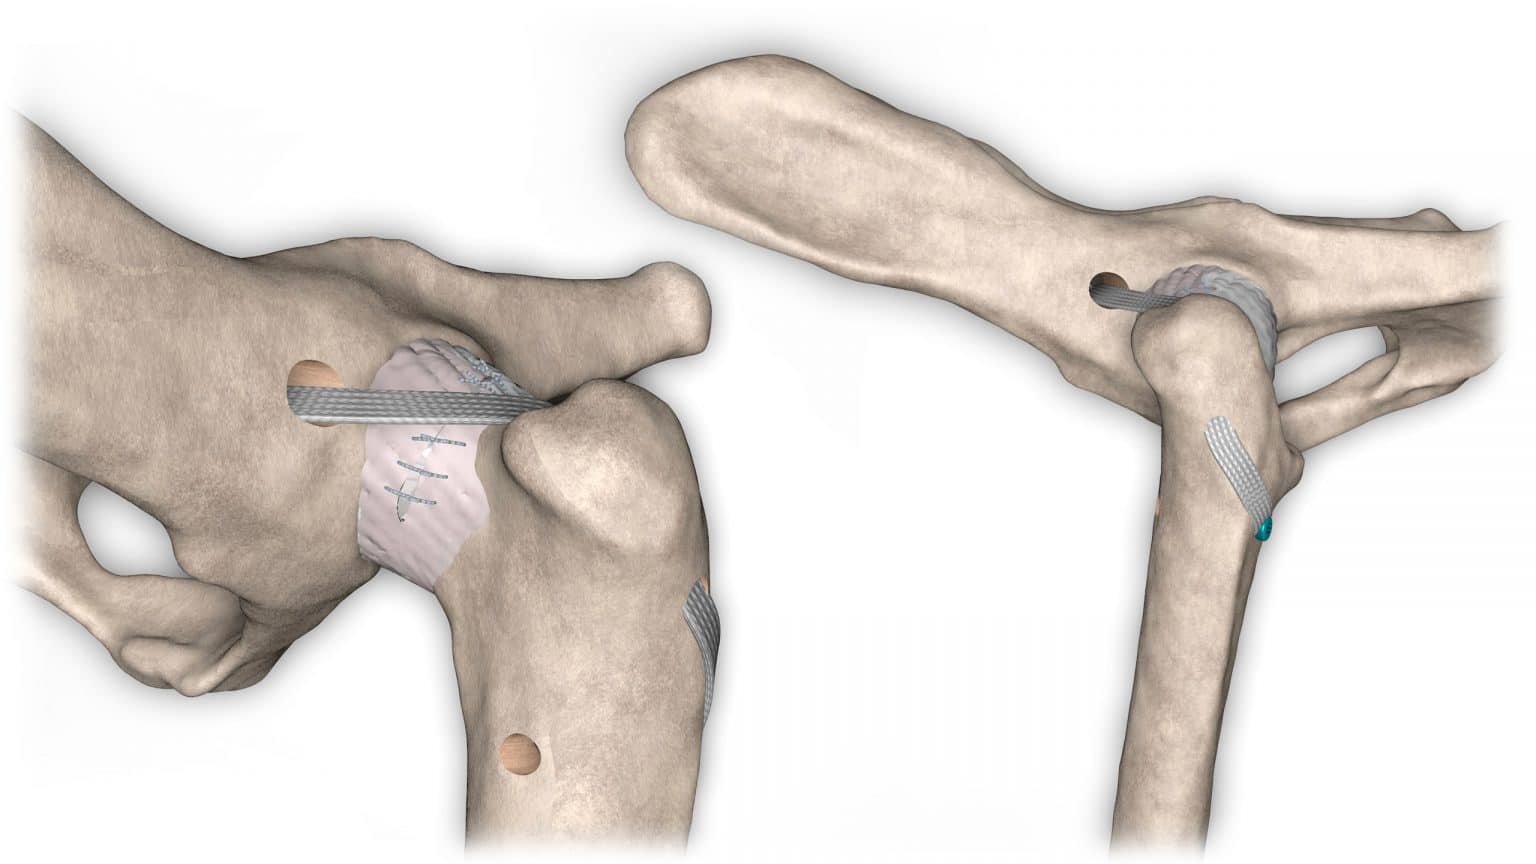

NOVALIG® je syntetický vaz, který lze použít k rekonstrukci vazů a rychlému obnovení jejich fyziologických funkcí.

V případě zkřížených vazů umožňuje intraartikulární rekonstrukci v izometrických bodech připojení, čímž obnovuje biomechaniku kolene a všechny funkce natrženého vazu.

V případě více vazů kolene (kraniální, kaudální, kolaterální) je možné pomocí NOVALIG® anatomicky rekonstruovat každý vaz.